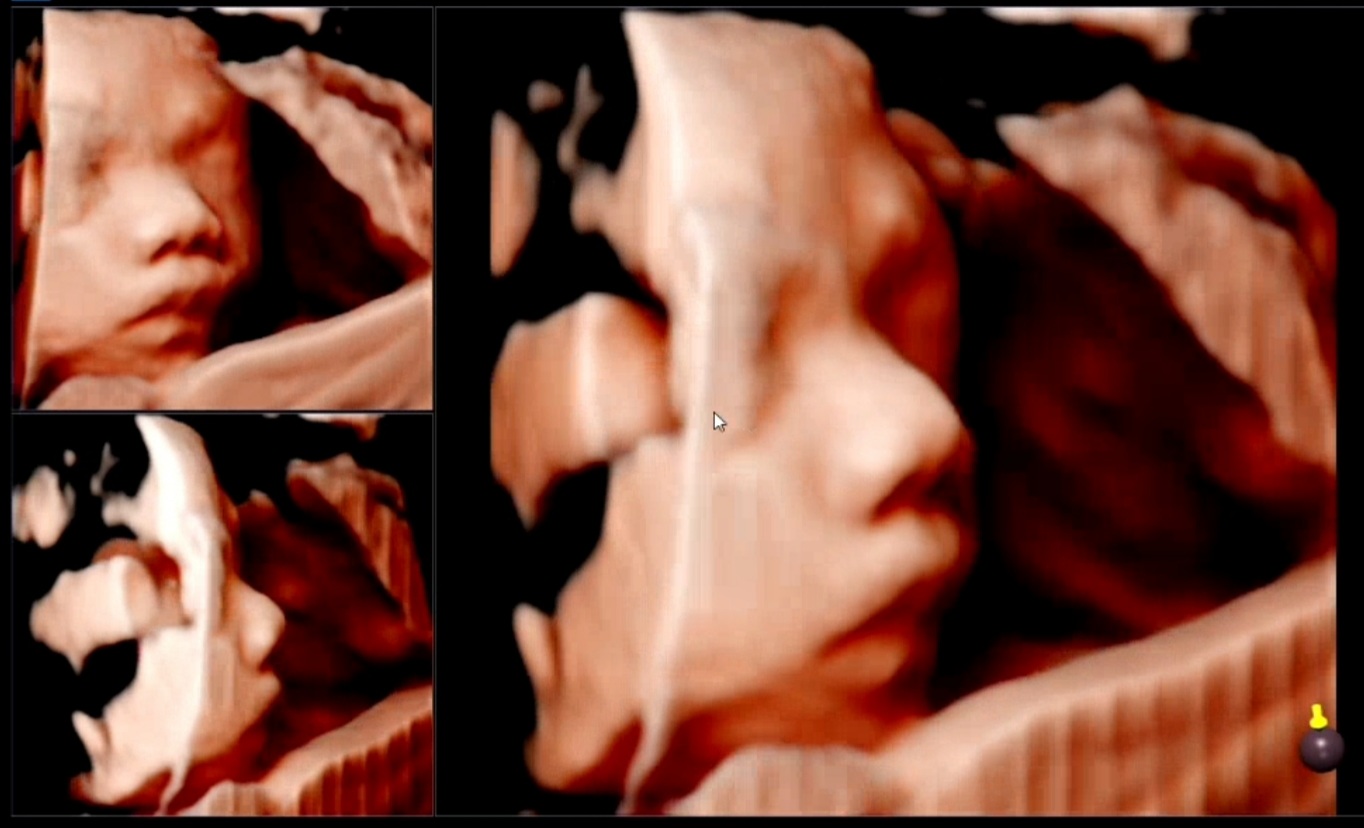

어제 29주 4일에 정기외래진료를 위해 서울성모병원에 다녀왔습니다. 29주 후에는 2주에 한 번씩 진료를 보라고 하셔서 지금은 2주에 한 번씩 치료를 하십니다. 28주차에 접어들면서 배가 많이 고파지고 아랫배가 월경통 같은 느낌이 들어서 혹시 모를 경우를 대비해 의료가방을 들고 다니다가 포장해서 가지고 갔습니다. 출발 직전에 심장이 너무 빨리 뛰고 또 과호흡을 해서 일이 너무 많아서 택시를 탔다. 초음파를 위해 들어갔다. 아기의 체중은 이미 1.5와 1.6입니다. 평균체중보다 2주나 컸어요..!! 요즘 중기부터 아침마다 사과를 먹기 시작했어요 2주만에 키가 컸어요 소고기와 과자를 너무 많이 먹은 탓인지. 2주전에 B-초음파 봤는데 내려오질 못하는데 하품하는거 보고 너무 귀여워서 오늘은 녹화하고 싶어서 베베 세이 바코드 가져왔는데 이번엔 아기들이 마주보고 그래서 나는 그녀에게 그것을 보여주지 않았습니다. 똑바로 누워있으면 죽을 텐데. 간호사는 내가 옆으로 누울 수 있다고 말했습니다. 큰 가방을 보고 교수님께서 왜 이렇게 짐이 많은지 물으셨고, 자주 배에 혹이 나는 최근 몸 상태를 말씀드렸더니 건강하다고 칭찬해 주셨습니다. 모호하기 때문에 입원하겠다고 말했고 Utrogestan 질정을 처방했습니다. 수축 테스트를 위해 일주일 후에 다시 오라고 말했습니다. 그는 또한 심실의 크기가 정상으로 유지되었고 주 수에 따라 모든 성장이 잘 자라고 있다고 말했습니다. 감사하게도 이맘때쯤이면 백일해 주사가 필요하다고 하셔서 백일해 주사와 갑상선 검사를 요청하셔서 채혈을 하기로 하셨습니다. 오늘의 의료비가 지난번보다 낮아질까요? 했는데 헐… 26만원 나왔어요. 남편이 비용을 지불했습니다. 감사해요. 임신테스트기 쿠폰이 다 떨어져서(융모막검사는 비싸다) 지금 내야 하는데 너무 비싸다. 그리고 열이 날 것 같아서 그 시간에 타이레놀을 먹게 했다. 참으면 아기에게 좋지 않다고 하더군요. . 그리고 채혈실로 가서 채혈을 하고 앉아서 기다렸다. 옆에 계신 할아버지께서 지금은 임신한 여성을 보기 힘들다고 하시니 참 애국심이 강하네요. 우리는 ㅋㅋㅋ 암튼 약 때문에 진통이 잦았는데 큰일 났다.